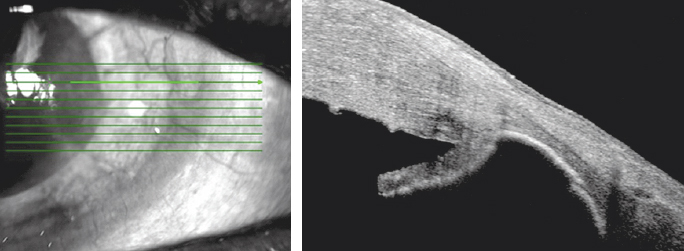

Измерения ВГД проведены у 39 пациентов с глаукомой и/или катарактой (22 женщины, 17 мужчин, средний возраст 62,34 ± 9,1 года, от 43 до 78 лет), с изменениями роговицы вследствие различной офтальмопатологии: посттравматические рубцы (5 глаз); кератотомические рубцы после рефракционных хирургических вмешательств, в том числе после сквозной кератопластики (6 глаз); дефекты роговицы в исходе язвенного процесса различной этиологии (4 глаза); эрозии роговицы (12 глаз); буллёзная кератопатия (7 глаз); деформации и лейкомы после хирургического лечения птеригиума или воздействия инфекционного агента (5 глаз). У 28 пациентов диагностирована первичная глаукома I–IV стадий или вторичная (постувеальная, неоваскулярная и др.), на 18 глазах ранее, в сроки от 15 лет до 6 мес., были выполнены 1–2 антиглаукомные операции, однако в зонах хирургического вмешательства не выявлялись фильтрационные подушки, которые могли бы повлиять на конгруэнтность поверхности глазного яблока и верхнего века. В 16 случаях пациенты получали местную гипотензивную терапию в разных сочетаниях лекарственных средств. Все глаза в различные сроки получали противовоспалительную и регенерирующую терапию по поводу заболевания роговицы. Основным из критериев включения в исследование пациентов было наличие патологии роговицы, препятствовавшей проведению пневмотонометрии и контактных методов измерения офтальмотонуса (рис. 2).

Рис. 2. Патологические изменения роговицы у пациентов

Fig. 2. Pathological changes of the cornea in patients